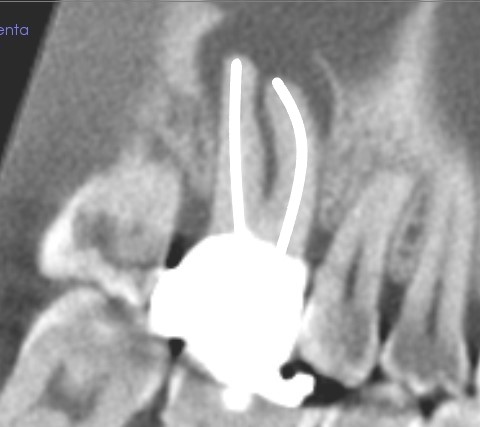

治癒傾向にある、穿孔による歯周組織の骨吸収

半年後のレントゲン写真です。

黒く映る骨が溶けた部分が小さくなり、治癒傾向にあるのが分かります。

今は、噛んでも、普通のときも、不調は感じないそうです。

こんな根管治療のやり直しは、

マイクロスコープとラバーダムを使う歯医者さんでないと、難しいと思います。

肉眼で行う根管治療のやり直しは、こんなケースでは避けた方がいいかもしれません。

肉眼では、根管の奥深くは見えにくいからです。